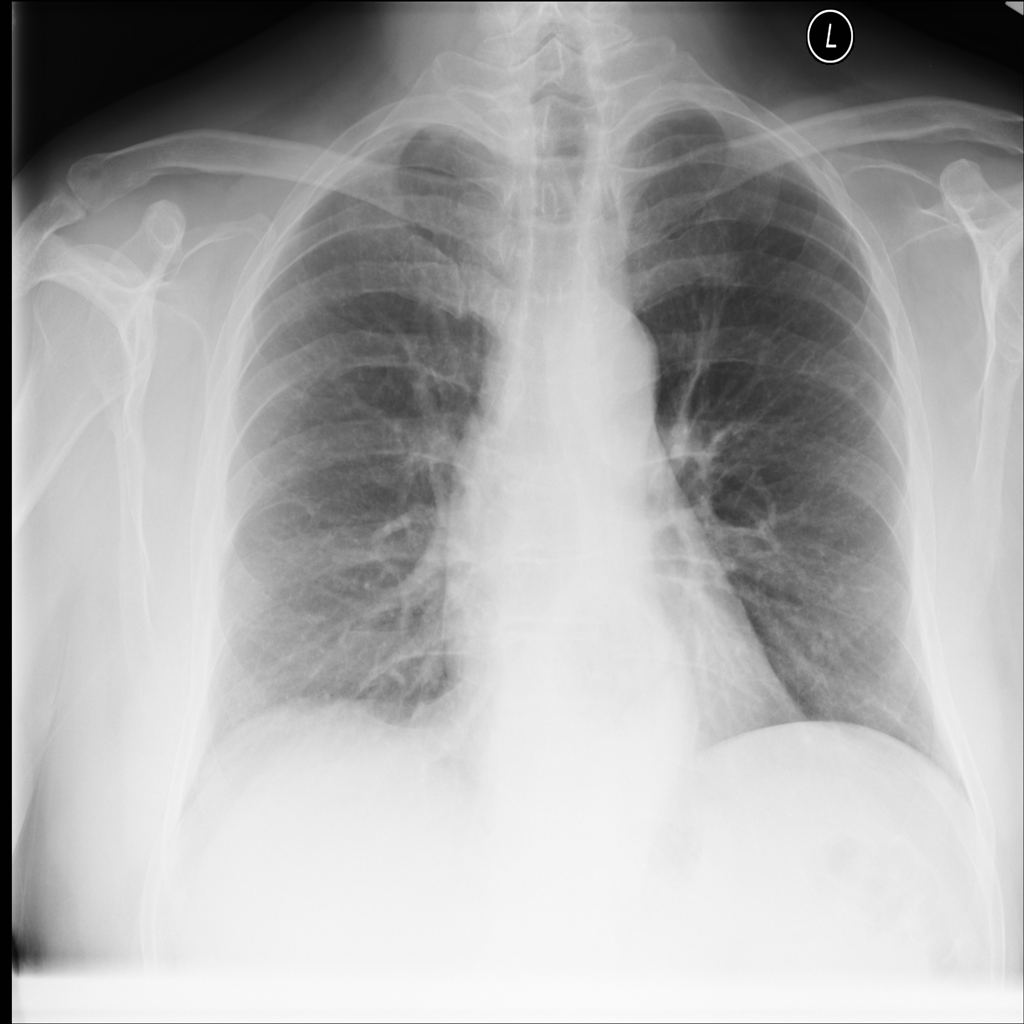

PAT-4F7E · IMG-000Hernia

PAT-4F7E · IMG-000

PA